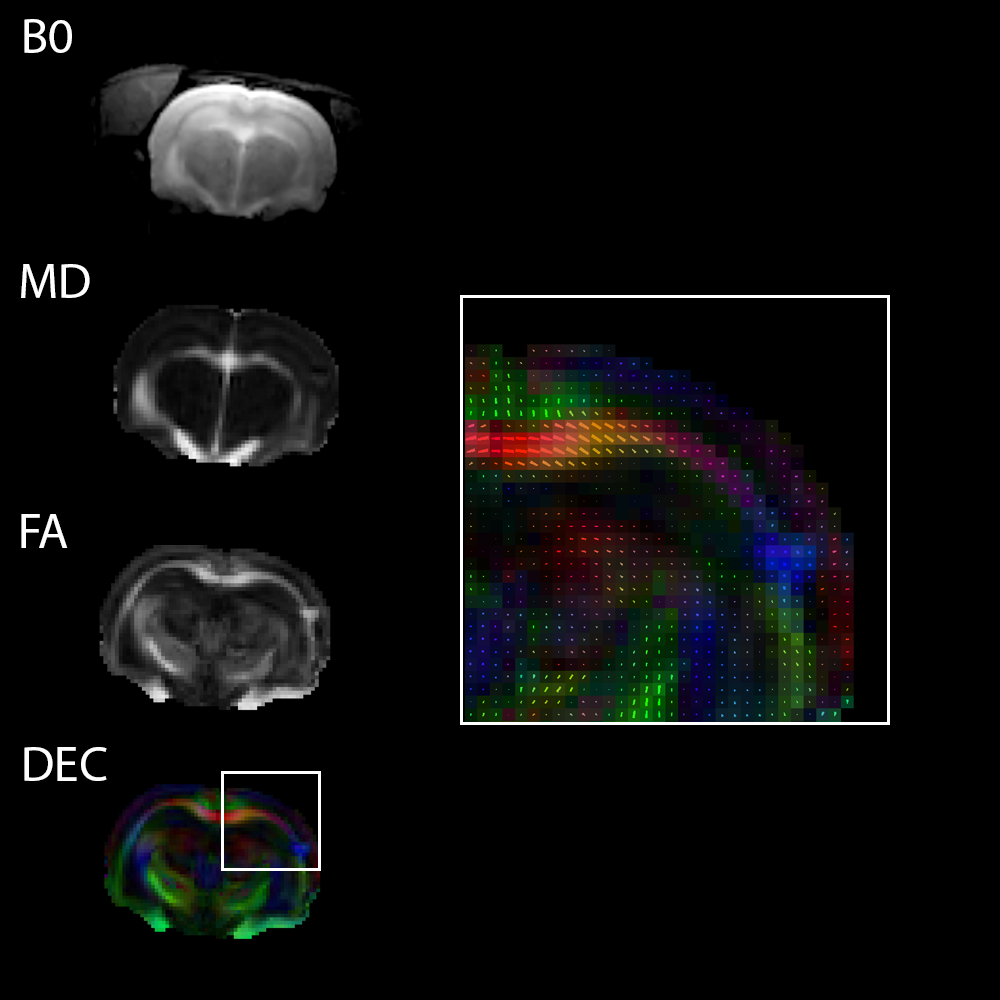

3T强度下的扩散张量成像技术

3T下大鼠脑部单次激发扩散张量成像(DTI EPI)

〉动物模型:Wistar大鼠

〉序列:

单次激发扩散张量成像(DTI)EPI,

矩阵大小:96x96

〉扩散方向:120,层厚:1mm

〉线圈: 72mm Tx/Rx体积线圈,用于传输和 30毫米柔性表面线圈,用于信号接收